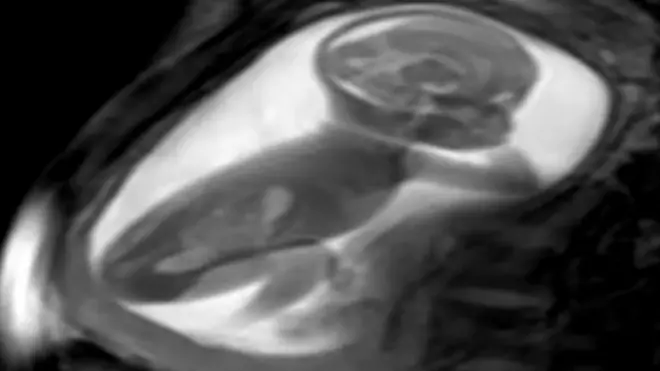

Doktori u njenom rodnom jugozapadnom gradu Satkira postavili su joj dijagnozu urođene srčane mane po imenu desktrokardija, kada je srce okrenuto na desnu stranu grudi umesto na levu.

Zajedno sa dekstrokardijom, Das je dobila i dijagnozu „situs inversus", još jednog retkog stanja u kom su krupni vitalni organi obrnuti u odnosu na njihove normalne položaje.

Njena jetra, pluća, slezina i želudac pronađeni su na suprotnim stranama u odnosu na njihov raspored na desnoj strani, praktično izokrenuti u odnosu na uobičajenu ljudsku anatomiju.

Prema studijama, dekstrokardija se dešava jednom na svakih 12.000 trudnoća.